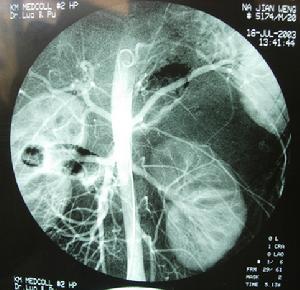

4.數字減影血管造影 可了解主要血管的受侵及腫瘤的主要供血動脈,有助於術中處理腫瘤的主要血管在行數字減影血管造影術的同時,如果發現腫瘤有主要滋養血管可同時進行介入治療和血管栓塞,使腫瘤壞死縮小,便於再手術。

由於腹膜後復發性腫瘤局部解剖關係發生改變、腫瘤大、位置深、操作空間小、容易傷及腹膜後大血管,再手術時出血量較大。術前對出血量要有充分估計並有足夠的備血量。才能保證手術的完成。如有條件,術前應行數字減影血管造影術檢查,找到主要供血動脈行栓塞治療可減少術中出血,但腫瘤惡性程度高血供豐富者,往往有多處供血動脈,栓塞止血效果往往不夠滿意。